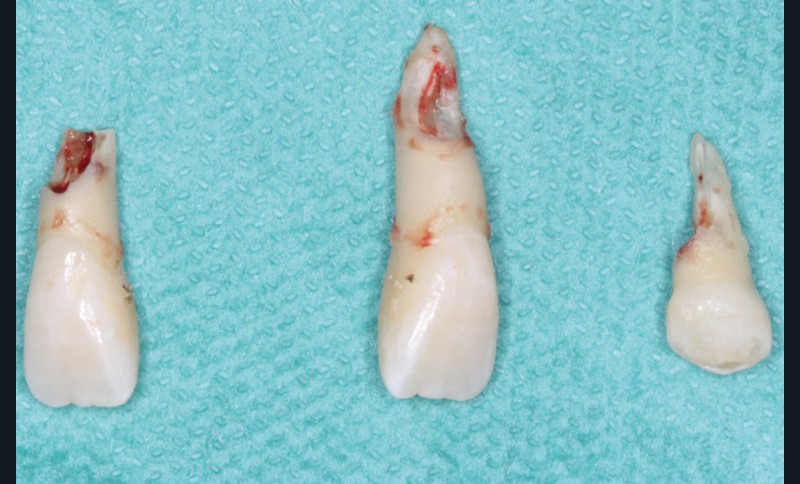

Le plan de traitement choisi comprend les extractions de 63, 12, 22, 34 et 44. Ce choix s’est porté d’une part sur le fait de la présence de résorptions très avancées de 12 et 22 et d’autre part sur la correction de la biproalvéolie facilitée par l’extraction de 34 et 44 qui ont par ailleurs un diamètre légèrement inférieur à 35 et 45.

Les extractions de 12, 22, 63, 34 et 44 ont été réalisées dans un premier temps. Un cache esthétique en résine composite a été élaboré à partir d’une clé en silicone obtenue sur les empreintes initiales et collé sur 11 et 21 afin de limiter l’impact psychologique de telles extractions (fig. 2a-b).